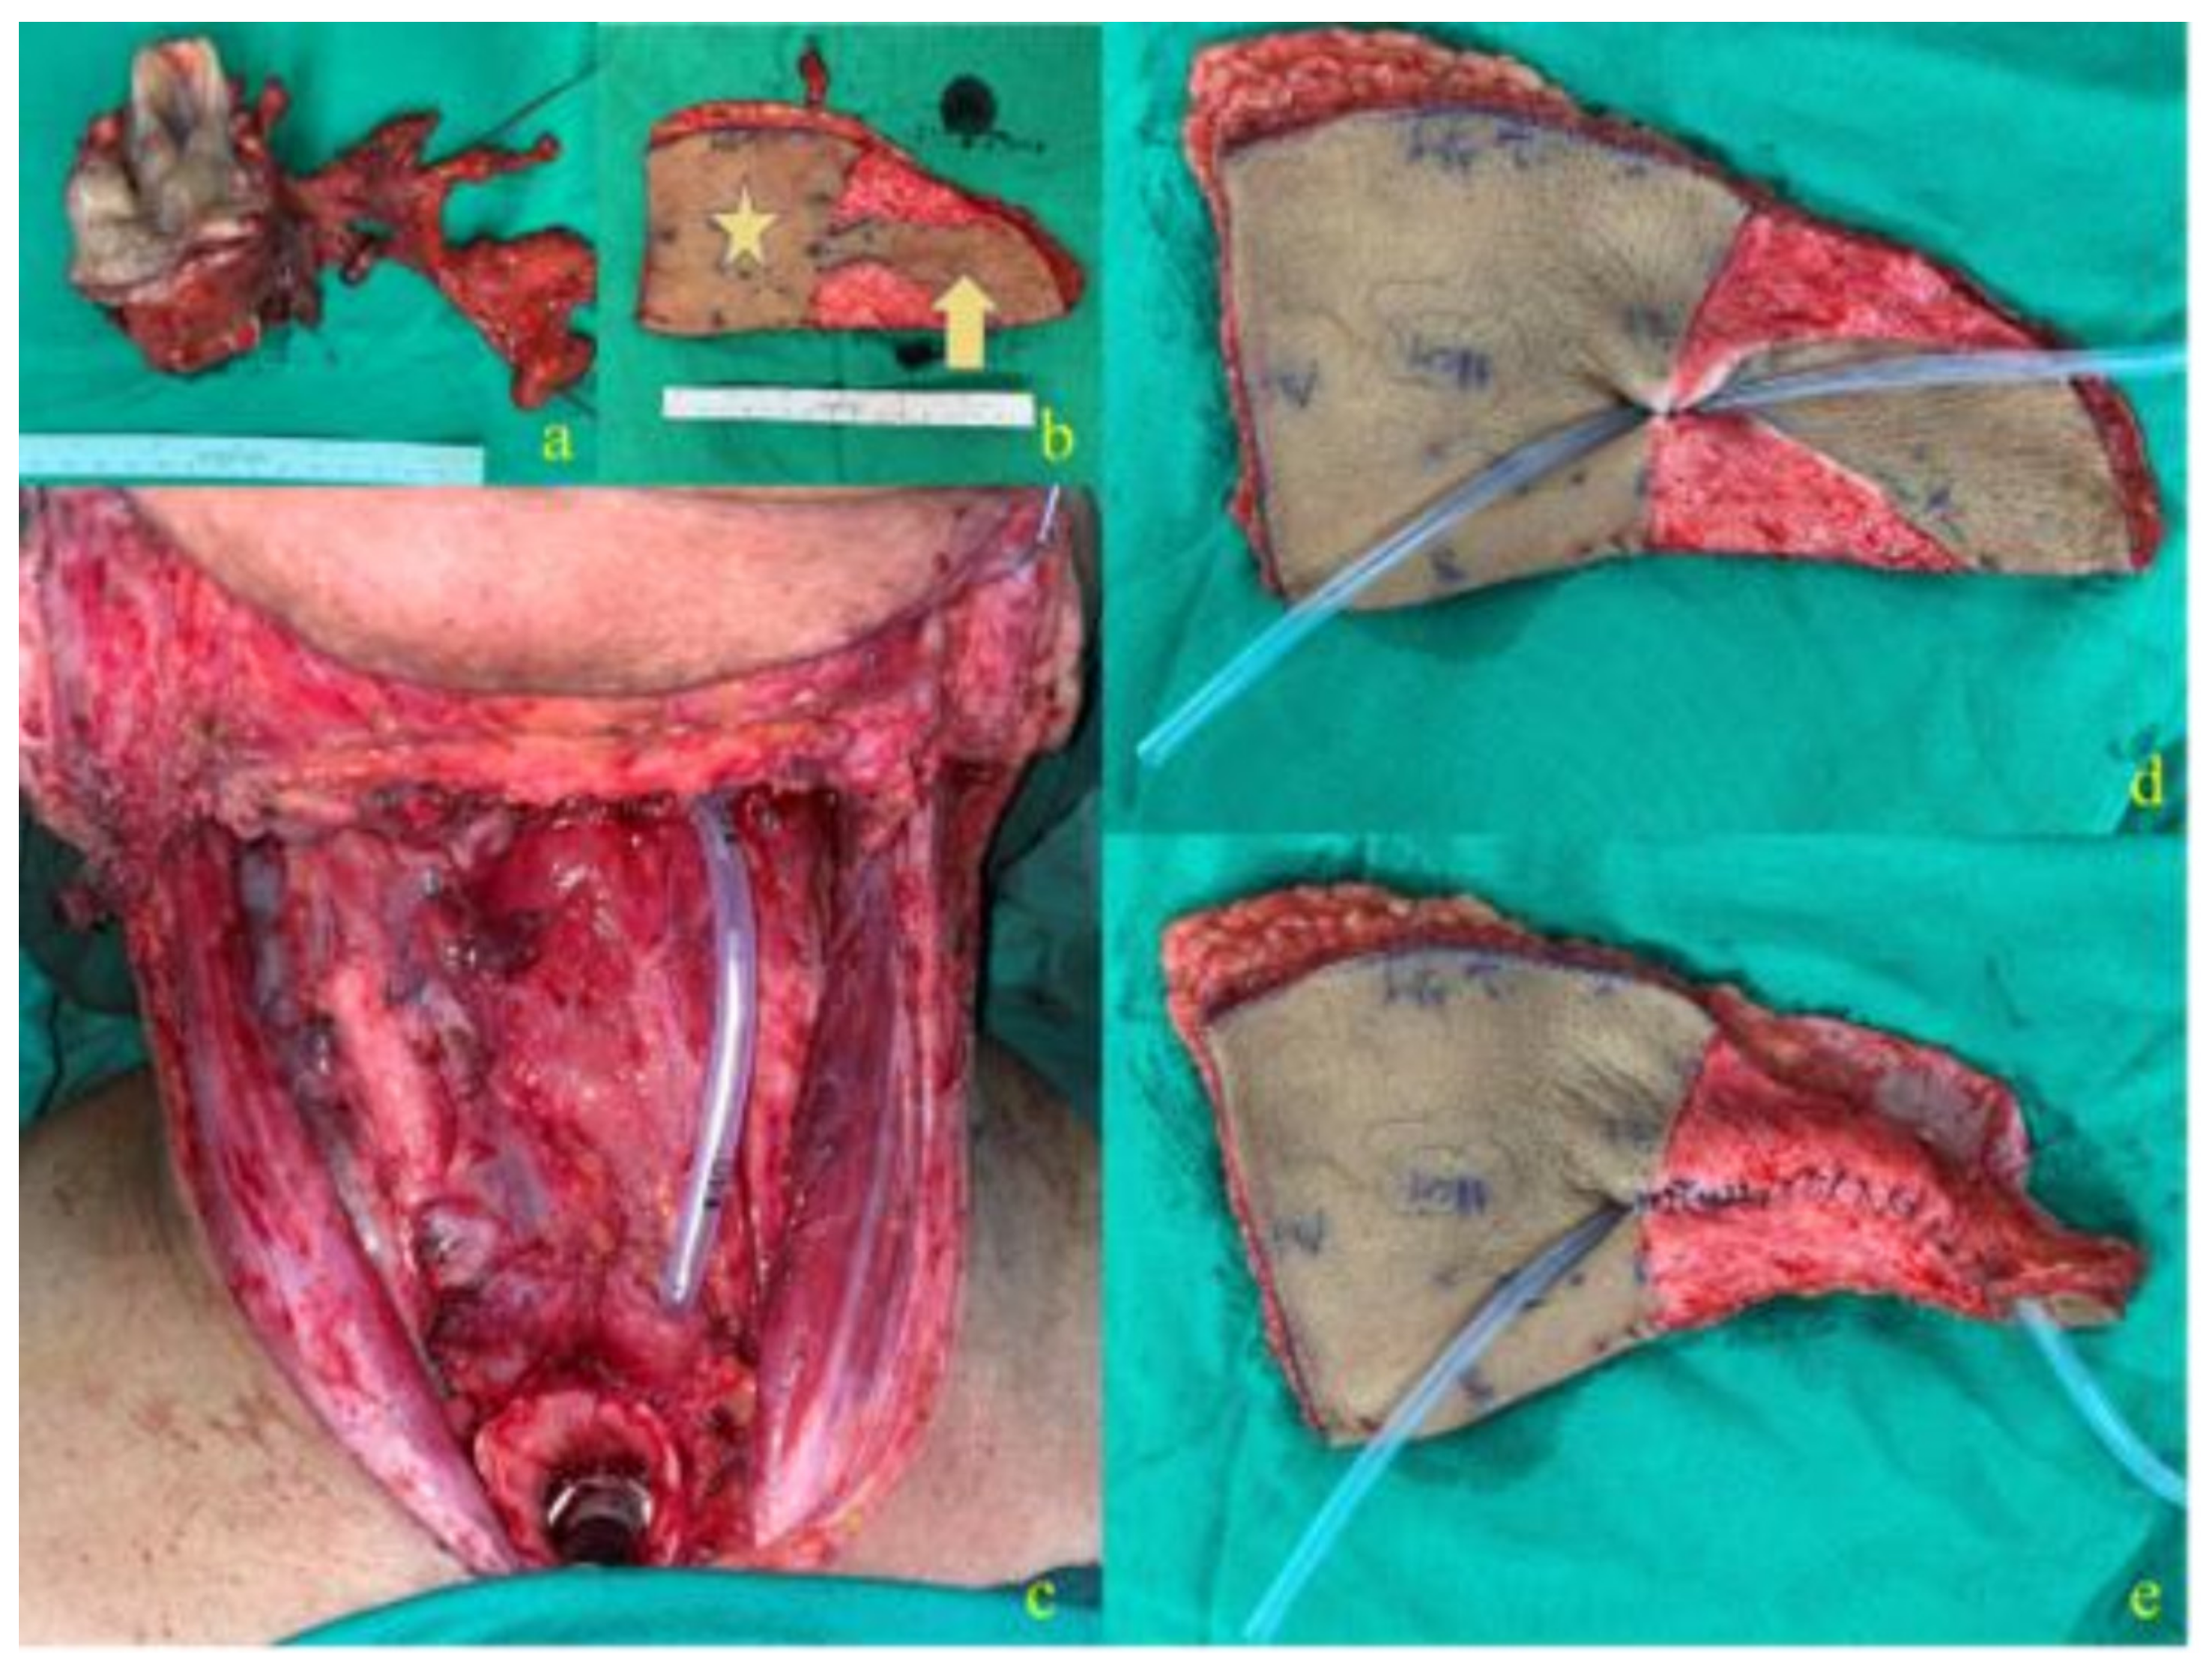

2.1. Surgical Technique

2.1.2. J-Flap Phonatory Tube